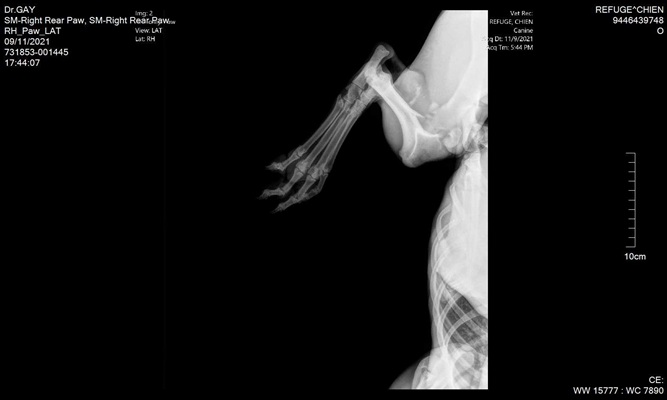

Mittelfußfraktur - OP am 22.11.2021

BRADLEY hat die OP gut überstanden und hat am 03. Dezember 2021 die Klinik verlassen können und ist bis zum Transport am 11. Dezember 2021 auf einer französischen Pflegestelle.